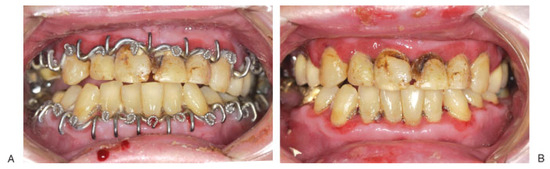

Mandibulo-maxillary fixation (MMF) screws are inserted into the bony base of both jaws in the process of fracture realignment and immobilisation. The screw heads act as anchor points to fasten wire loops or rubber bands connecting the mandible to the...